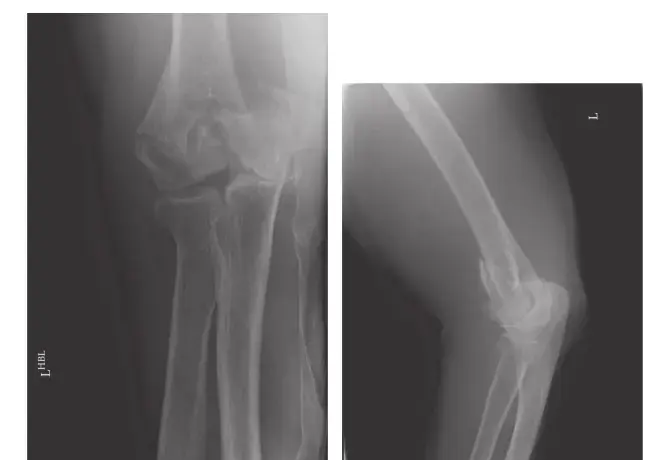

- الأشعة السينية (X-rays): تساعد في الكشف عن التغيرات العظمية، مثل التهاب المفاصل أو انزلاق الفقرات، ولكنها لا تظهر الأنسجة الرخوة كالأقراص الغضروفية أو الأعصاب.